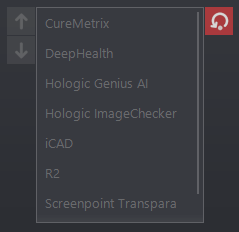

Prioritize the supported CAD

The CAD list order setting is included in the default profile and can be copied to new and existing user accounts.

Support ScreenPoint Transpara CAD

The viewer supports ScreenPoint’s Transpara CAD objects.